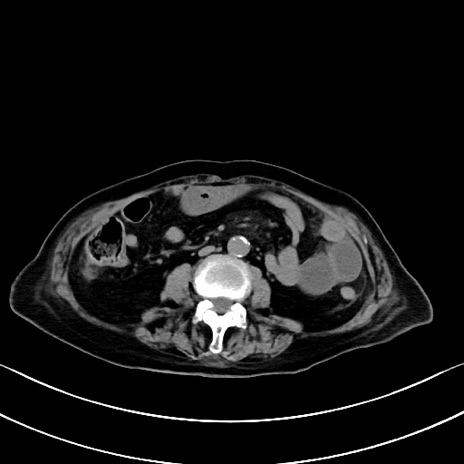

横断像